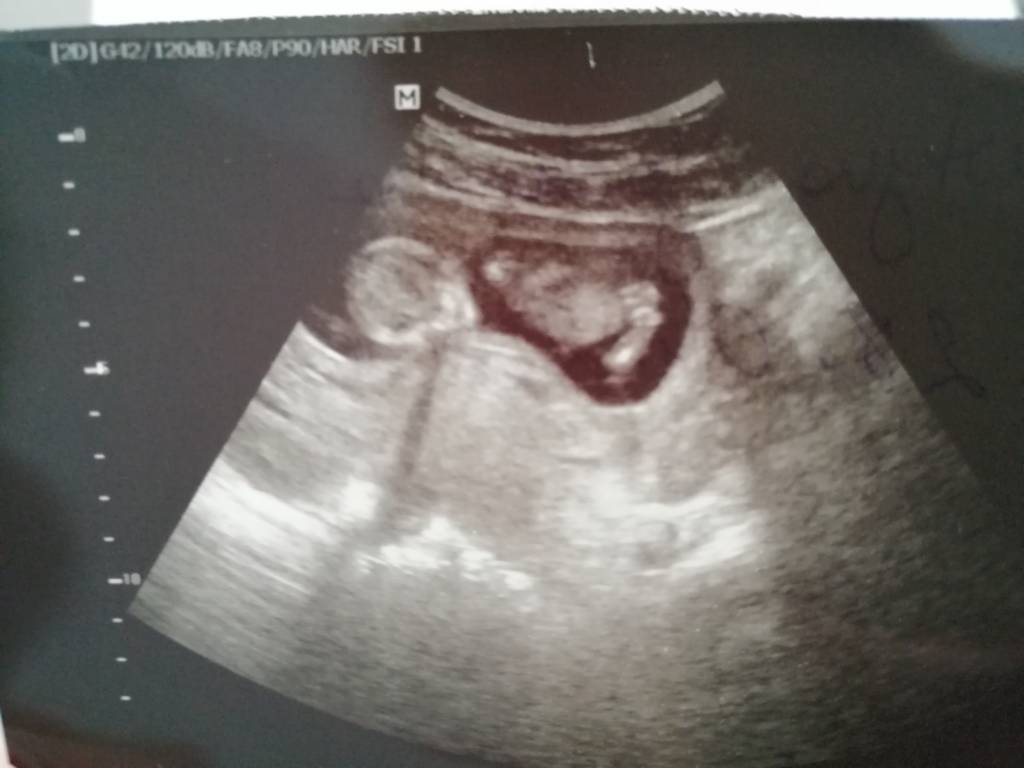

No dotarlam w końcu do ostatniej strony hehe, ja po wizycie opóźnionej i nerwowej ale jestem. Z dzidziusiem wszystko dobrze, podskakuje sobie we wszystkie strony i jedno ujęcie ma trochę nóżki rozłożone i zapytałam o płeć to mówiła, że jak dziecko pokaże ale wzięła lupkę i pokazała mi na jednym zdj ze jakby może byc chłopiec bo widać trochę takie jakby jajeczka [emoji2960] ale kazała się tym nie sugerować bo roznie może być i jeszcze tak dobrze nie widac. A nerwowo było bo babka na korytarzu mnie wytrąciła z równowagi bo ona przyszła przede mną a ja po niej ale ja miałan wizytę ustalona na 9:30 a ona umówiła się z lekarka przed 10 bo do 10 przyjmuje, więc nie miała konkretnej godziny a skoro ja miałam tzn ze byłam zapisana jako pierwsza i w ciąży a ona jakaś starsza na cytologię sobie przyszła i się drze na mnie, tak mnie wkurzyła, że się z nią kłóciłam aż pielęgniarka wyszła a i tak weszłam ją jako pierwsza, nawet pacjentki od innej lekarki z korytarza mnie poparły i do niej mówią że kobiety w ciąży lekarka przyjmuje jako pierwsze... [emoji2356][emoji2356][emoji2356]

Piękne maleństwo!No dotarlam w końcu do ostatniej strony hehe, ja po wizycie opóźnionej i nerwowej ale jestem. Z dzidziusiem wszystko dobrze, podskakuje sobie we wszystkie strony i jedno ujęcie ma trochę nóżki rozłożone i zapytałam o płeć to mówiła, że jak dziecko pokaże ale wzięła lupkę i pokazała mi na jednym zdj ze jakby może byc chłopiec bo widać trochę takie jakby jajeczka [emoji2960] ale kazała się tym nie sugerować bo roznie może być i jeszcze tak dobrze nie widac. A nerwowo było bo babka na korytarzu mnie wytrąciła z równowagi bo ona przyszła przede mną a ja po niej ale ja miałan wizytę ustalona na 9:30 a ona umówiła się z lekarka przed 10 bo do 10 przyjmuje, więc nie miała konkretnej godziny a skoro ja miałam tzn ze byłam zapisana jako pierwsza i w ciąży a ona jakaś starsza na cytologię sobie przyszła i się drze na mnie, tak mnie wkurzyła, że się z nią kłóciłam aż pielęgniarka wyszła a i tak weszłam ją jako pierwsza, nawet pacjentki od innej lekarki z korytarza mnie poparły i do niej mówią że kobiety w ciąży lekarka przyjmuje jako pierwsze... [emoji2356][emoji2356][emoji2356]

Gratulacje! Już mu mało miejsca zostałoNo dotarlam w końcu do ostatniej strony hehe, ja po wizycie opóźnionej i nerwowej ale jestem. Z dzidziusiem wszystko dobrze, podskakuje sobie we wszystkie strony i jedno ujęcie ma trochę nóżki rozłożone i zapytałam o płeć to mówiła, że jak dziecko pokaże ale wzięła lupkę i pokazała mi na jednym zdj ze jakby może byc chłopiec bo widać trochę takie jakby jajeczka [emoji2960] ale kazała się tym nie sugerować bo roznie może być i jeszcze tak dobrze nie widac. A nerwowo było bo babka na korytarzu mnie wytrąciła z równowagi bo ona przyszła przede mną a ja po niej ale ja miałan wizytę ustalona na 9:30 a ona umówiła się z lekarka przed 10 bo do 10 przyjmuje, więc nie miała konkretnej godziny a skoro ja miałam tzn ze byłam zapisana jako pierwsza i w ciąży a ona jakaś starsza na cytologię sobie przyszła i się drze na mnie, tak mnie wkurzyła, że się z nią kłóciłam aż pielęgniarka wyszła a i tak weszłam ją jako pierwsza, nawet pacjentki od innej lekarki z korytarza mnie poparły i do niej mówią że kobiety w ciąży lekarka przyjmuje jako pierwsze... [emoji2356][emoji2356][emoji2356]